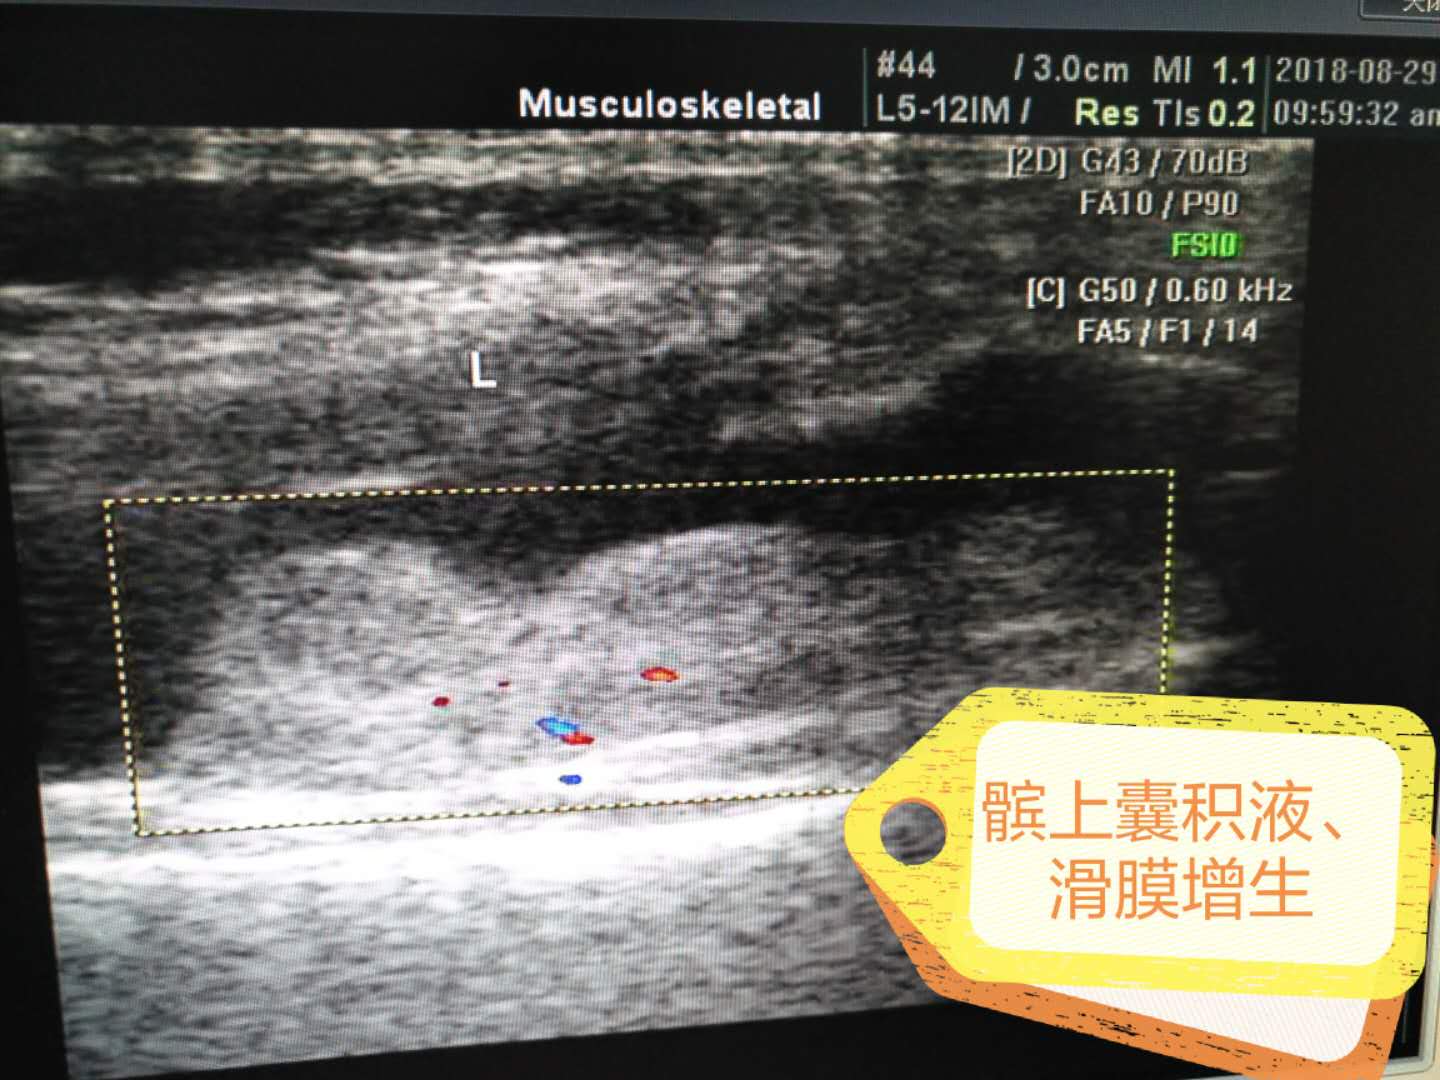

髕上囊積液、滑膜增生

科室專(zhuān)業(yè)特色:產(chǎn)科四維、腔內超聲、胃超聲、肌肉、肌腱、關(guān)節、外周神經(jīng)超聲等。優(yōu)勢:無(wú)創(chuàng )、無(wú)輻射、實(shí)時(shí)、便捷。